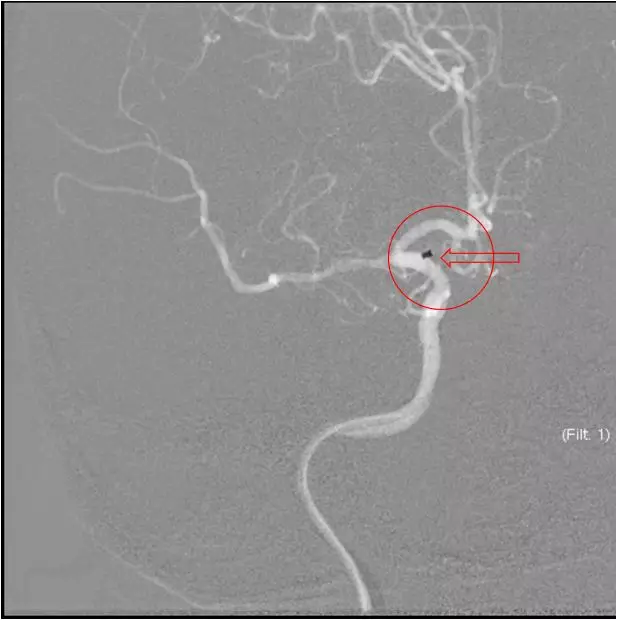

患者症状逐渐加重,头颅MRA示右侧大脑中动脉闭塞,是本次病灶责任血管,目前患者在取栓时间窗内,有行桥接动脉机械取栓指征。与患者家属沟通后全麻下行右侧大脑中动脉取栓术。手术风险及相关注意事项向患者家属告知。

立即DSA(08-03日 13:24分)

赛诺 2.0*15mm球囊扩张

赛诺 2.0*15mm球囊扩张

再次与家属沟通病情,交代支架植入风险,家属表示理解,准备支架解脱

5MIN后

再次观察10MIN后